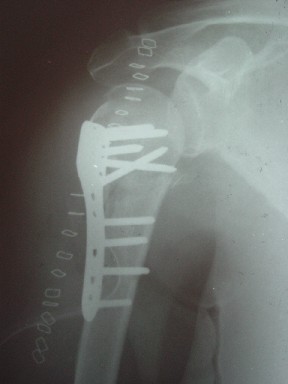

Re: Перелом шейки плеча

В этом плане Locking plate очень хороша так как позволяет начать движения сразу после операции.

Клинические снимки - 3 недели после операции